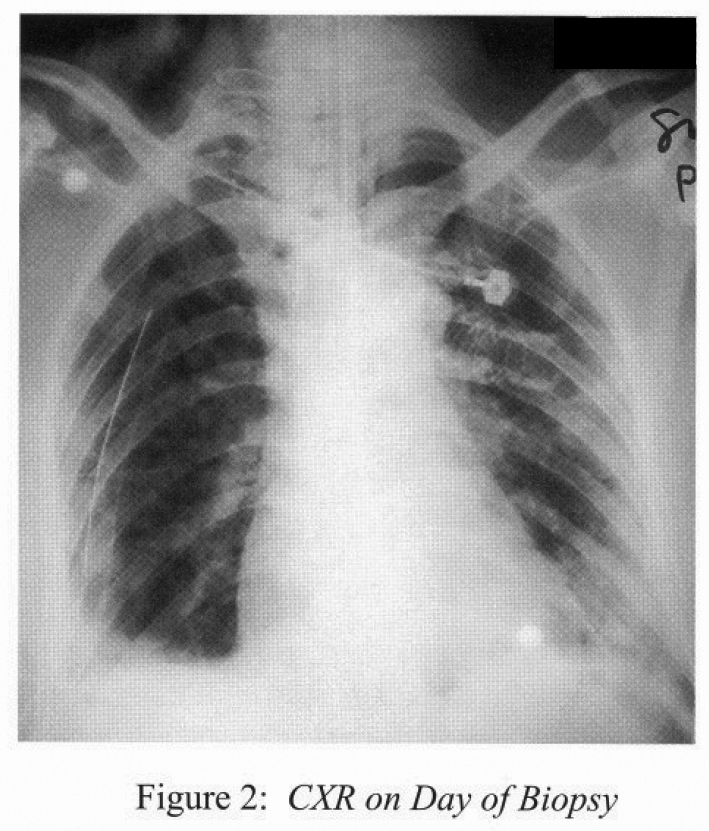

Chest radiograph on the day of biopsy was shown (Figure 2).